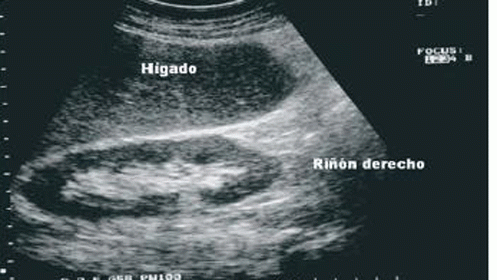

Ecografía renal en Hospital Jerez Puerta del Sur, gestionado por Gesmedi.

El ultrasonido renal, también denominado "ecografía renal", es un examen seguro e indoloro en el cual se utilizan ondas sonoras para obtener imágenes de los riñones, los uréteres y la vejiga.

Los riñones son un par de órganos con forma de guisante, que están ubicados cerca de la parte posterior de la cavidad abdominal, justo encima de la cintura. Se encargan de eliminar los productos de desecho de la sangre y de producir orina. Los uréteres son conductos delgados que transportan la orina hacia la vejiga.